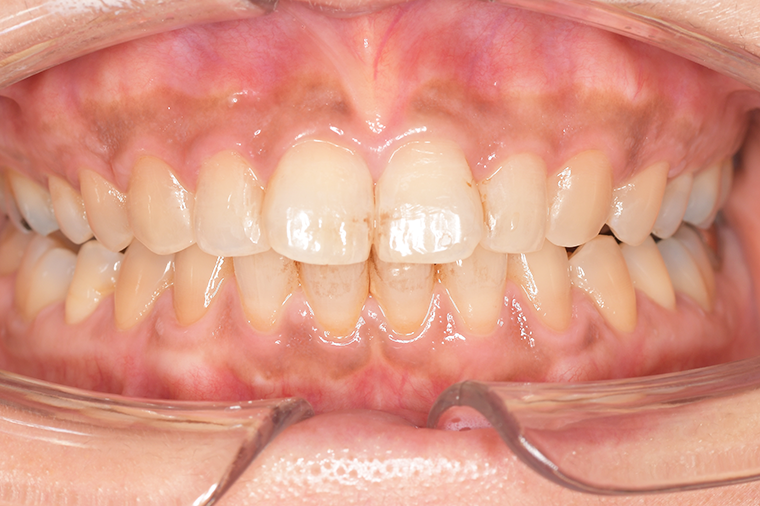

CASE 3

Before

After

基本情報

| 年齢・性別 | 30代・女性 |

|---|---|

| 主訴 | 定期検診 |

| 治療内容 | PMTC |

| 治療期間 | 60分 |

| 治療費 | 5,750円 |

| リスク・副作用 | しみる可能性があります。 |

| 治療方針 | PMTCでステインの除去。 |

| 担当者所見 | ステインが付きやすいため、3カ月毎の定期検診で除去する。 |